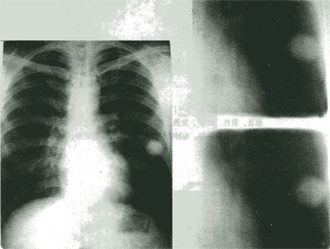

2.血行播散型肺结核(X线表现为三均特点)

(1)肺野均匀分布。

(2)1.5~2mm大小。

(3)密度相同的粟粒状病灶。